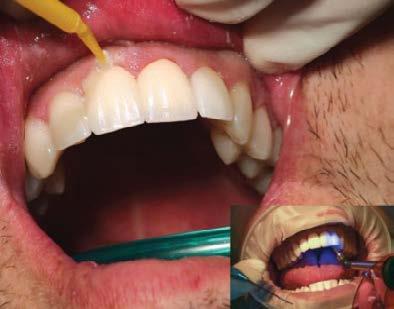

Estudio de caso

El paciente se presentó después de varios años de sufrir una herida traumática en sus dientes anterio res superiores. Las piezas 11 y 21 tenían varias fracturas, así como el borde incisal de la pieza 12. Por lo que él deseaba mejorar su estética bucal, y yo quería asegurarme de restaurar la funcionalidad y resisten cia también. El paciente necesitaba completar su tratamiento en un cor to periodo de tiempo, por ello debí realizar ajustes en mi flujo de traba jo. (Figura 1).

Durante la segunda cita le mostré al paciente su nuevo diseño de sonrisa en el modelo de encerado fabricado por Glidewell.

Cita 2. Aprobación del encerado de diagnóstico

Durante la segunda cita le mostré al paciente su nuevo diseño de sonrisa en el modelo de encerado fabricado

por Glidewell, permitiéndole exami nar el diseño estético de la restaura ción final propuesta (Figura 4).